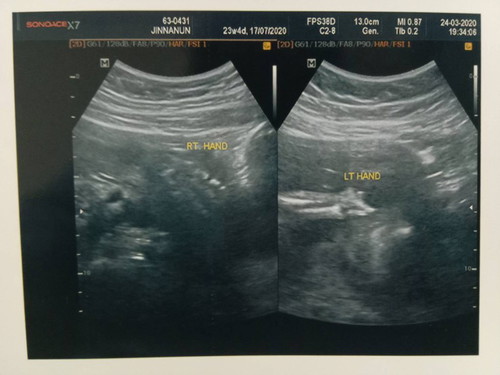

อัตตราซาวด์แล้วพบความผิดปกติมือซ้ายของลูกไม่ครบ

เริ่มรู้ตัวว่าประจำเดือนไม่มาเดือนแรก ก็ตรวจและไปฝากครรภ์ทันที อายุครรภ์6สป.ตั้งแต่เดือนพฤศจิกายน 62 ตรวจเลือด ผลออกมาปกติ จากนั้นหมอก็ได้ให้แต่ยาบำรุง ไม่ได้อัตตราซาวด์ดูพัฒนาการการของทารกเลย จนสัปดาห์ที่20 (27/2/63)หมอนัดซาวด์ แต่หมอบอกไม่เจออะไร ไม่เห็นอะไร อย่าถามเพศนะแม่ เลยถามหมอกลับว่า อย่างอื่นปกติมั้ย ตอบไม่ได้ชัดเจน เอาเป็นว่า ปกตินะแม่ ซึนอนลงไม่ถึง5นาที ตอนนั้นแครงใจมาก ท้องลูกแรกด้วย ทำไมหมอไม่ไล่ ลำดับหัว ลำตัว หัวใจ แขนขา ให้ฟังเลย จึงตัดสิ้นใจไปซาวด์คลีนิคนอกที่ผ่านมา เพื่ออยากดูพัฒนาการลูก วันที่23/03/63 คุณหมอที่คลีนิคเเจ้งว่าน้องไม่มีพัฒนาการทางด้านมือข้างซ้าย ซ๊อคมาก ดูทั้ง4มิติ จนหมอแนะนำให้กลับำปหาหมอที่ฝากครรภ์แล้วปรึกษา จะมีวิธีการรักษาหรือพัฒนาการยังไง 2/4/63 หมอนัดตรวจครรภ์ ปกติ จึงยื่นเอกสารที่ซาวด์ให้หมอดู หมอไม่ทำอะไรให้ ถามอะไรก็ตอบไม่ได้แม้แต่จะซาวด์หรือฟังเสียงหัวใจลูกก็ไม่ทำ ได้แต่บอกว่าเดียวหมอจะนัดหมอที่เขามีความชำนาญเรื่องความผิดปกติให้ จนเราต้องย้ำว่าขอเร็วที่สุด คือวันที่7/04/63 หมอซาวด์เกือบ1ชม. ก็พบความผิดปกติของมือซ้ายลูกจริง คือนิ้วมือ มาไม่ครบ ต้องตรวจละเอียด ถึง สมองและไขสันหลัง ว่ามีโรคอะไรซ้อนอีกมั้ย หมอบอกแต่ว่าเสียใจกับเรื่องมือ ตอนนี้อายุครรภ์25สป.ทำอะไร ไม่ได้แล้ว ถ้ารู้ก่อนหน้านัเน หมออาจจะหยุดการตั้งครรภ์ นอกจากจะต้องพยุงและแข็งแรงผ่านไปให้ได้ ติดตามต่อเนื่อง จนคลอด เป็นแค่มือก็ส่งรักษาต่อที่หมอกระดูก หมอยังให้คำตอบชัดเจนไม่ได้ เบื้องต้น ปากไม่แหวก มันเศร้ามาก ซ๊อคมาก อยากให้มันเป็นแค่ฝันร้าย ลูกคนแรก ไปฝากครรภ์ตั้งแต่รู้ว่าแม่ ไม่เคยผิดนัด หมอไม่ทำอะไรให้เลย ยังต้องนัดต่อถี่ๆ เพื่อดูอาการลูก ว่าจะมีโรคอื่นแทรกซ้อนอีกมั้ย อยากถามว่ามีใครพอจะแนะนำ คุณหมอ หรือให้แม่ทำอะไรได้บ้างระหว่างที่ได้แต่รอ หมอ ซาวด์ อยากให้ลูกเกิดมาครบ32 ตอนนี้เจ็บปวด หัวใจ ทำใจไม่ได้เลย อยากให้ลูกเกิดมามีครบ ถ้าเอามือของแม่ไปต่อมือของลูกได้แม่ก็อยากทำ?